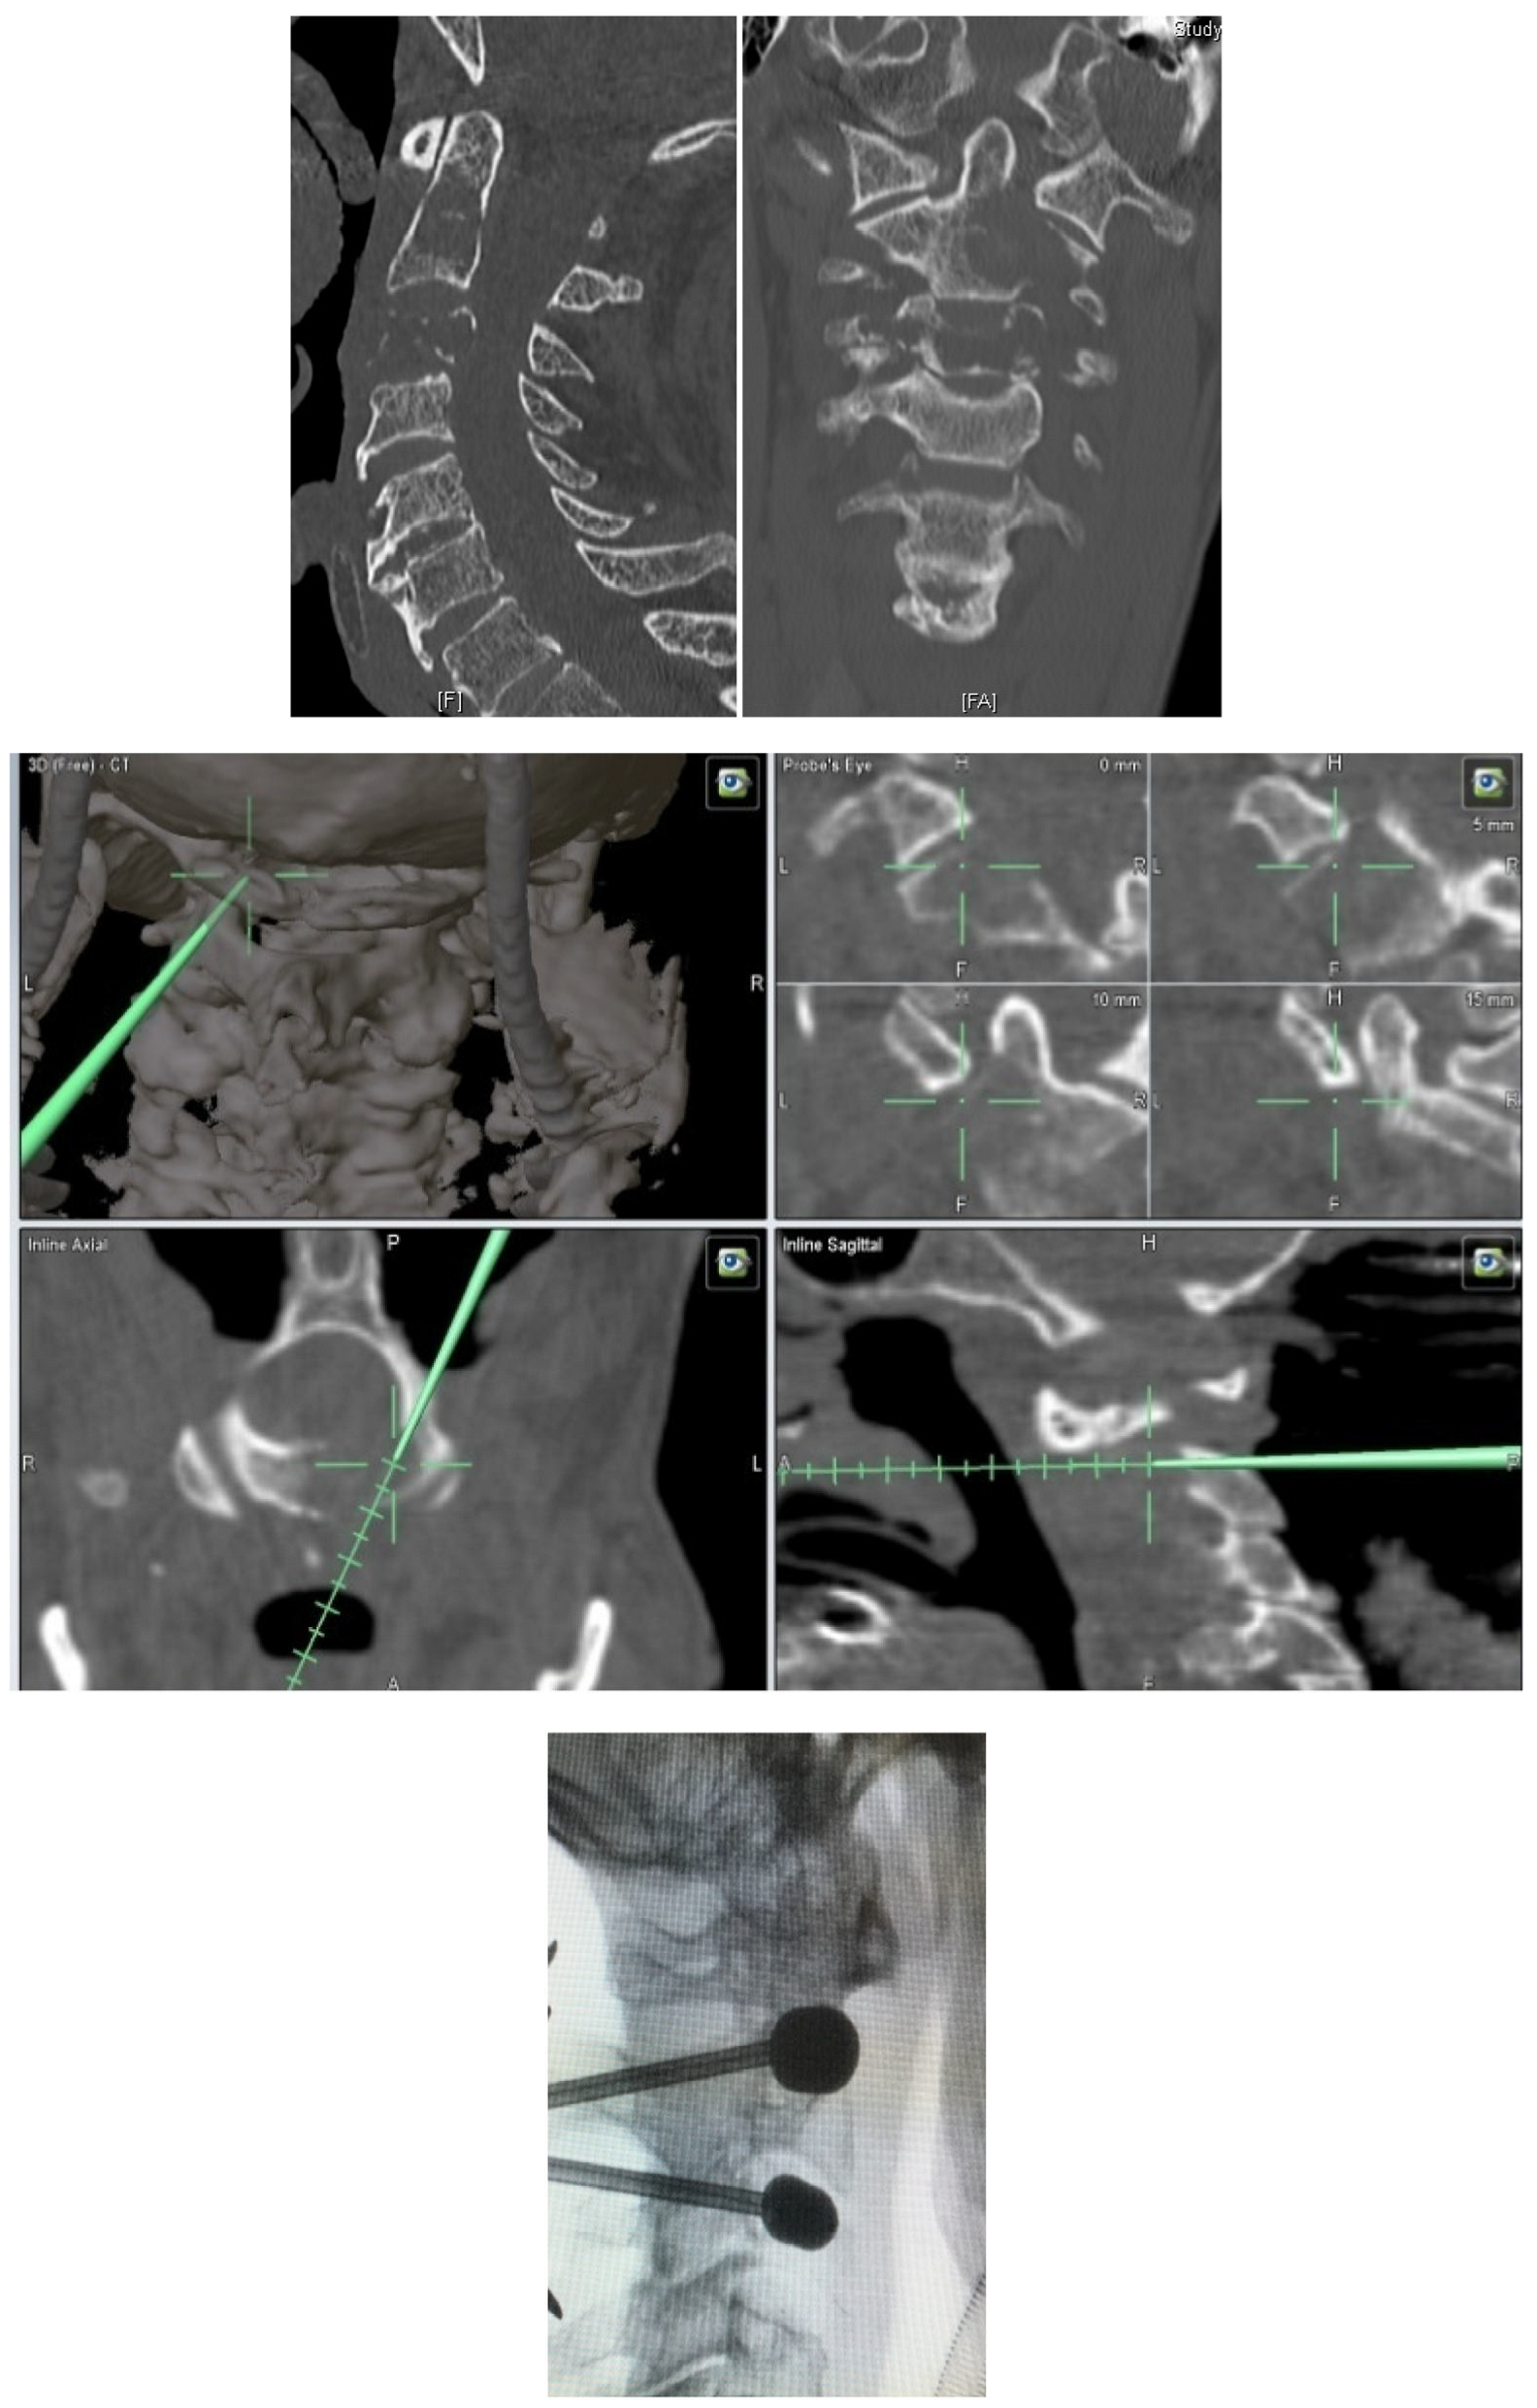

- Metastatic lesions of C1 are extremely rare, and their treatment by percutaneous cement augmentation is considered to be a technically challenging procedure due to complex anatomy. We also performed percutaneous kyphoplasty in a painful osteolytic lesion located on the left lateral mass of C1 through a posterolateral approach using a 3D CT scan intra-operative navigation system and fluoroscopy (Figure 3) [22].

- Florea, S.M.; Farah, K.; Meyer, M.; Dufour, H.; Graillon, T.; Fuentes, S. The interest of intraoperative scanner coupled to neuronavigation in traumatic or oncologic fractures of the cervical and upper thoracic spine requiring vertebral body height restoring procedures. Neurochirurgie 2020, 66, 240–246. [Google Scholar] [CrossRef]

- Meyer, M.; Farah, K.; Graillon, T.; Boissonneau, S.; Dufour, H.; Fuentes, S. Minimal Invasive Percutaneous Kyphoplasty of C1 Lytic Lesion Using an Intraoperative 3D Imaging-Based Navigation System and Fluoroscopy. J. Surg. Res. 2020, 3, 419–427. [Google Scholar] [CrossRef]